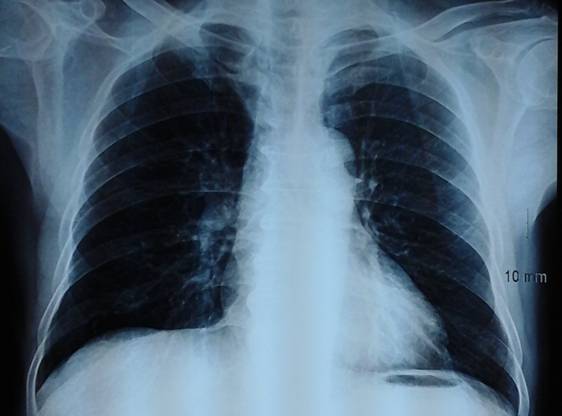

-          Chụp X- Quang tim phổi ngực thẳng: chưa phát hiện tổn thương bất thường

Hình 4: Hình ảnh chụp X- Quang tim phổi thẳng